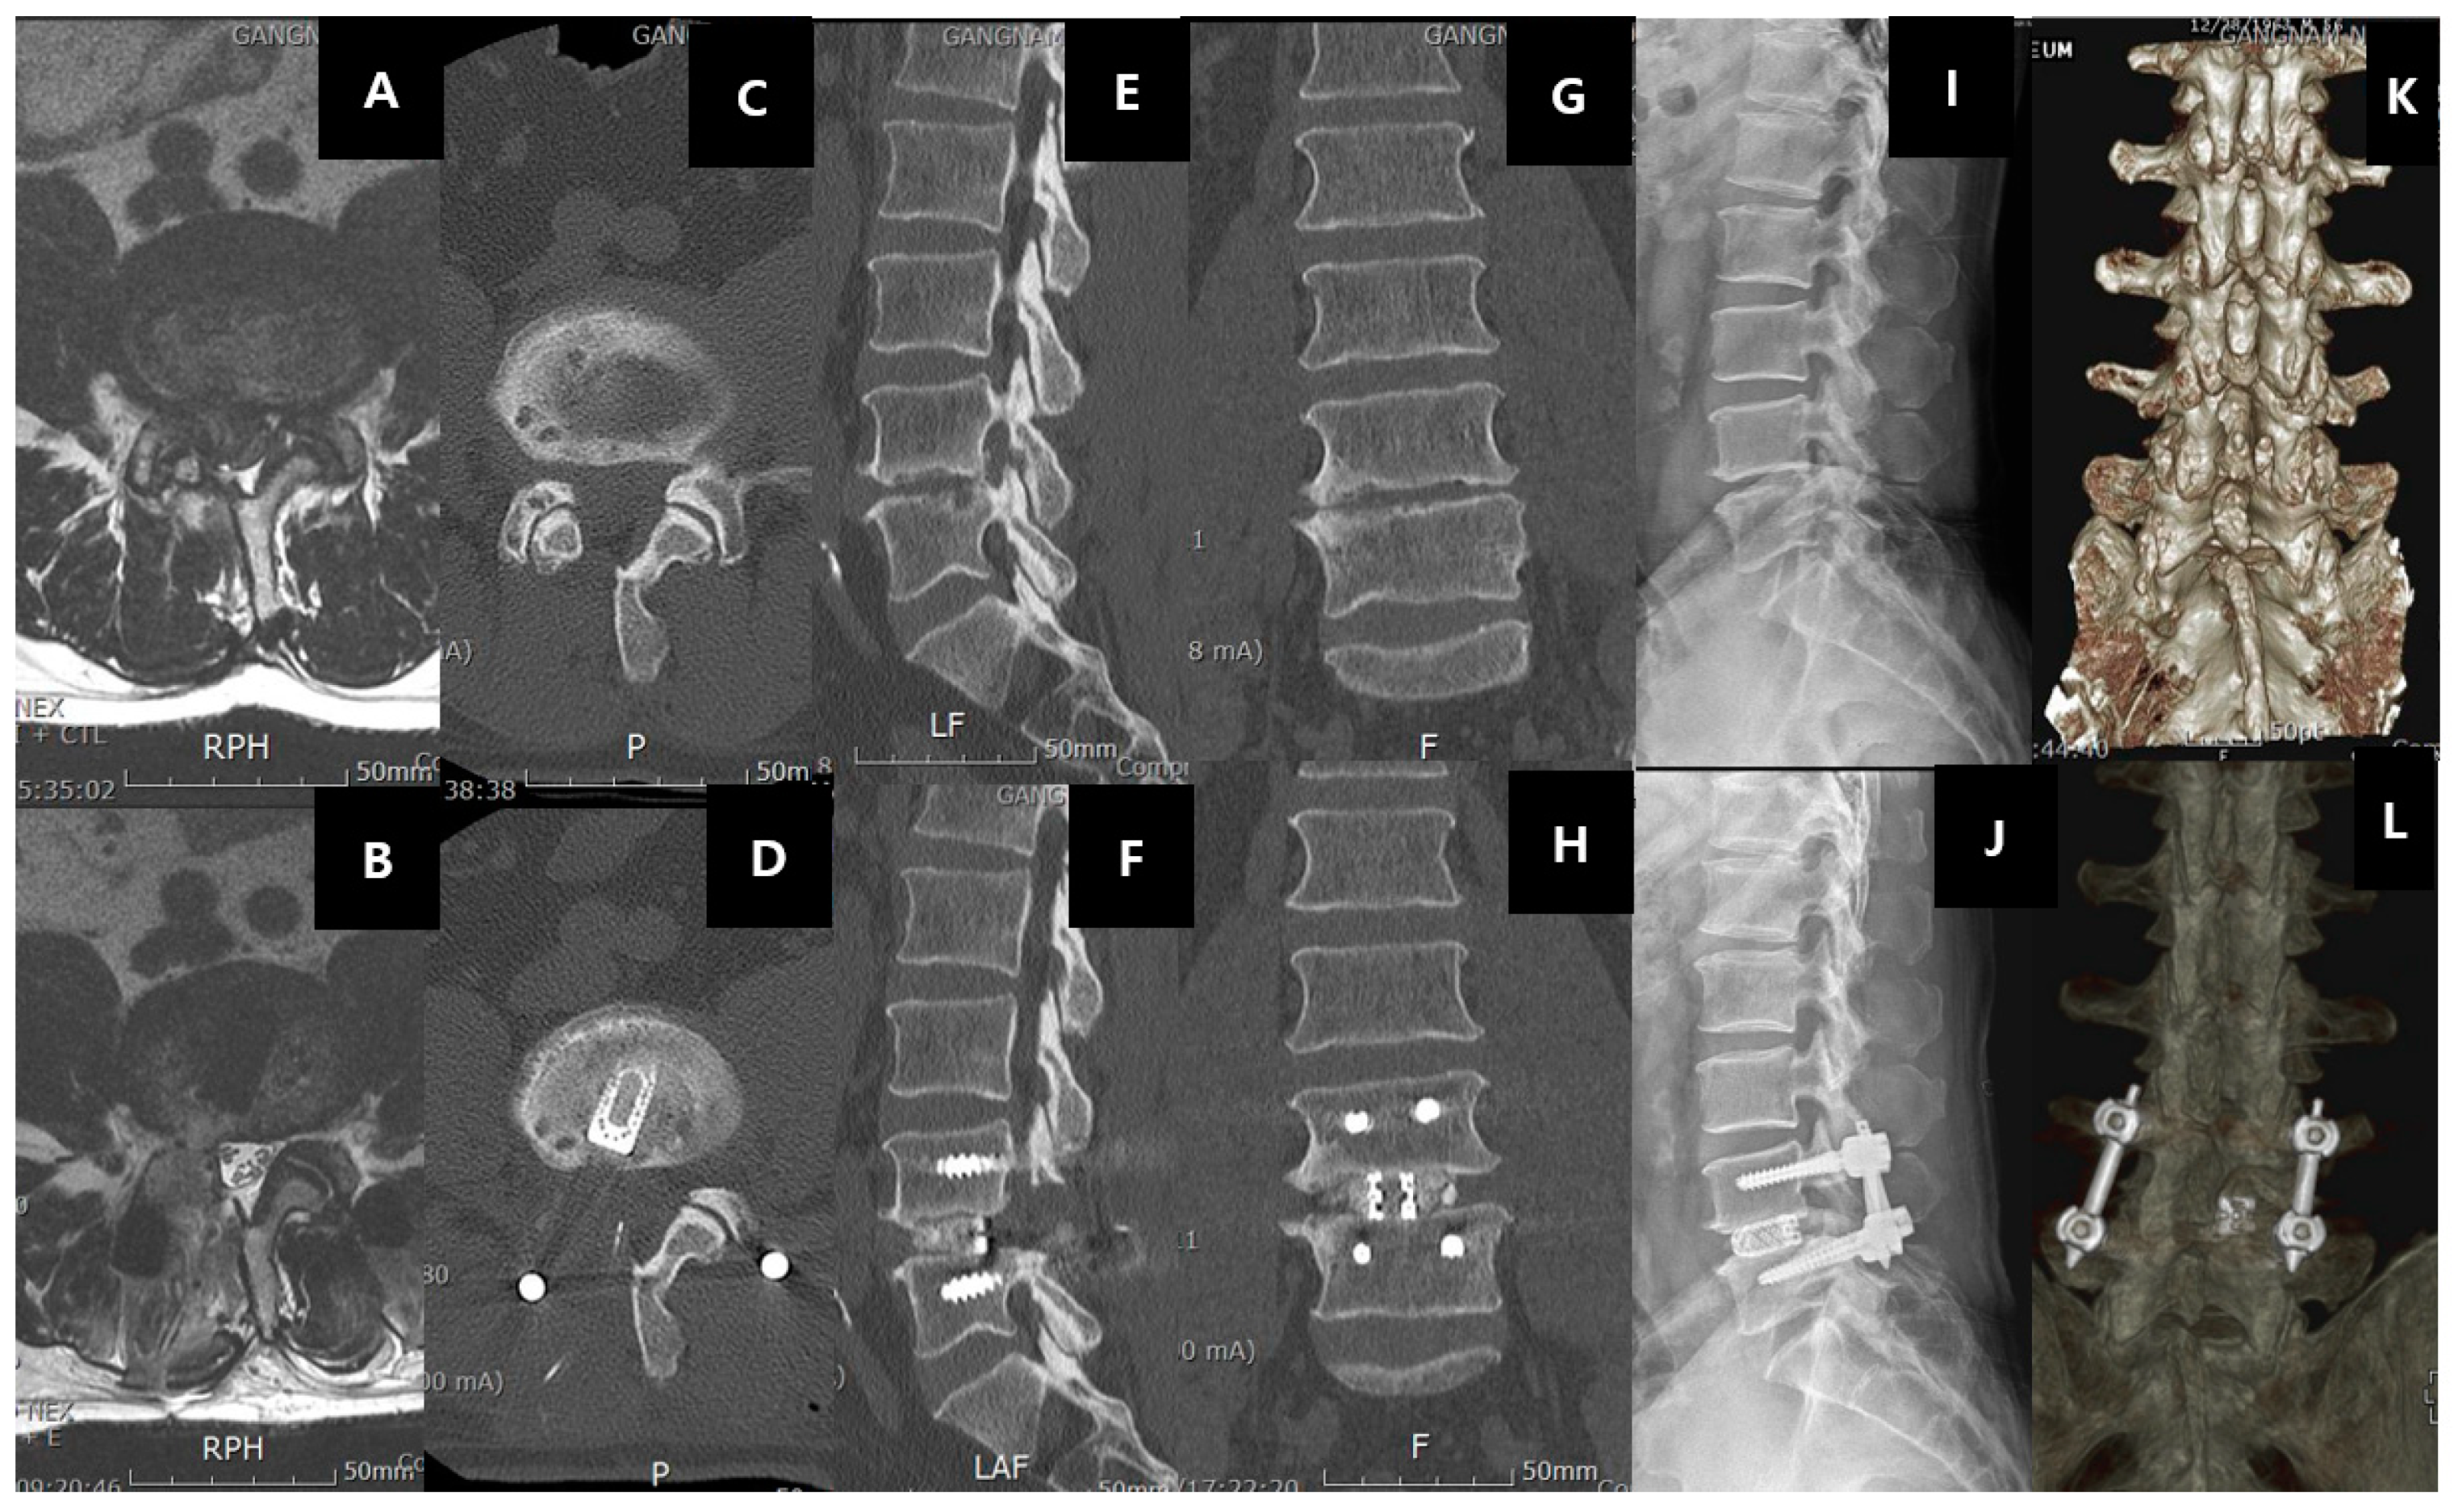

Spinal fusion surgery is a procedure to join two or more vertebra into one single structure (Figure 7). Spinal fusion typically involves (a) the removal of the joint cartilaginous substance, (b) followed by insertion of a material that has a combination of osteoinductive, osteoconductive, and osteogenic properties. The common substances used are autograft from bone harvested from the patient, allograft from bone banks, bone morphogenic proteins, and other calcium-based substances [169,170,171]. (c) Stabilization of the construct with instrumentation. Successful fusion ensures no movement between the two vertebrae and hence prevents further pathological enlargement of the facet joint, disc bulge, and buckling of the ligamentum flavum, which compress the neural elements. Placement of an interbody cage is a common method of fusion in spine surgery, which can increase the foraminal height by raising the space between the vertebrae [172,173]. The main indication for spinal fusion is similar to that of spinal decompression, with an additional element of instability either as a complication of the disease process or as an anticipated result of surgery (for example, excess bone removal in a revision decompression, which will cause instability). It can also be performed for degenerative disc disease without spinal stenosis. However, it should be done with stringent indication of selected cases who have failed most if not all forms of conservative management.

Figure 7.

Right-sided L4/5 recurrent disc herniation after previous open laminotomy and discectomy 2 years ago, the patient underwent uniportal endoscopic transforaminal lumbar interbody fusion of right L4/5(ETLIF). A shows the recurrence of disc herniation with facet arthritis in the MRI axial cut of L4/5. B shows the same axial cut with left transforaminal lumbar interbody fusion showing resection of the facet joint and cage in an optimal position. C and D show the pre and post-operative status of the right facet. Note the previous right L4 laminotomy in C, the facet was resected, and the cage introduced in an optimal position as shown in D. E and F show the sagittal view of the pre and pos-operative status. Note the increase in the foraminal height and intervertebral height as a result of the right L4/5 ETLIF. G and H show the increase in the coronal disc height pre and post-operatively in right L4/5 ETLIF. I and J show the pre and post-operative standing neutral XR with the L4/5 interbody cage and standard posterior inserted pedicle screws in L4 and L5. K and L show the 3D reconstruction of pre and post-operative right L4/5 ETLIF.

There are various terms and nomenclature of the various spine procedures can be confusing to young surgeons and scientists involved in spine-related research. In summary, all three types of surgeries (decompression, fusion, and disc replacement) are sub-classified according to (a) the degree of exposure, such as open or minimally invasive; (b) the direction of the approach to the spine, such as the posterior, posterolateral, transforaminal, direct lateral, oblique lateral, and anterior approach [174,175,176,177,178]; (c) in fusion surgery, the type of fusion, such as interbody and posterolateral; (d) in the decompression surgery, the amount of bone removed, such as laminectomy, laminotomy, and foraminotomy; and (e) the instrumentation method and approach required, such as percutaneous pedicle screw fixation, open posterior pedicle screw fixation, and cortical bone trajectory screws. Hence, a typical description of an open approach from the posterior direction with removal of the full lamina and spinous process of lumbar five lamina for a lumbar five–sacral one spinal stenosis is termed posterior open laminectomy of lumbar five vertebra. While the minimally invasive uniportal endoscopic transforaminal approach to fuse the lumbar five sacral one disc is termed posterior uniportal endoscopic transforaminal lumbar interbody fusion (Figure 7). A lumbar five sacral one interbody fusion if done from the posterior approach with standard pedicle screw insertion from the posterolateral direction is called open posterior lumbar five sacral one lumbar interbody fusion. While the same fusion procedure using cortical bone trajectory screws is termed open posterior lumbar interbody fusion with cortical bone trajectory fixation. There are many acronyms, such as ALIF (anterior lumbar interbody fusion), OLIF (oblique lumbar interbody fusion), XLIF (extreme lateral lumbar interbody fusion), TLIF (transforaminal lumbar interbody fusion), PLIF (posterior lumbar interbody fusion), and MidLIF (midline lumbar interbody fusion, which essentially means posterior lumbar interbody fusion with cortical bone trajectory screws fixation), etc.